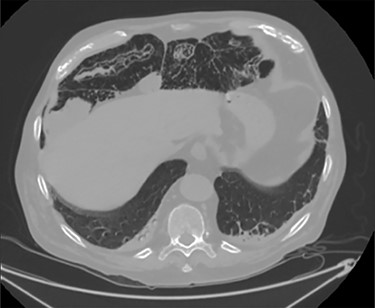

PCI was ultimately identified retrospectively using lung window settings.

PCI first documented by Du Vernoy in 1783 [4] refers to the intraoperative or radiological findings of intramural gas-filled cysts in the bowel wall (Fig. 4). PCI can easily mimic pneumoperitoneum on radiological imaging as CT, being a very sensitive examination, may show even minimal circumferential gas collections outside the bowel lumen or misrepresent some findings [5]. Liu et al. [6] found that PCI was misdiagnosed as a surgical abdomen in up to 27% of cases resulting in unnecessary operation. It is important to differentiate idiopathic PCI with a secondary form of this condition known as pneumatosis intestinalis which is not in fact a disease but a rare finding characterized by the presence of gas in the submucosal and/or subserosal of the bowel wall that may result from an underlying pathological process (Table 2). PCI has a reported incidence in general population of 0.03% on autopsy series and up to 0.37% in CT series. Its prevalence is still unknown [7]. However, Adachi et al. [8] in a retrospective, single-center study found 24.7% of PCI cases in the selected group affected by pneumoperitoneum. PCI involves most commonly the small and large bowel (respectively 42% and 36% of cases; in 22% is concomitantly present), but could also involve the mesentery and omentum [7]. Physiopathology remains still unclear although some hypotheses have been proposed such as: the ‘mechanical theory’ where an increased pressure of intraluminal gas secondary to mechanical problems breach the mucosal or serosal layers (i.e. blunt trauma, persistent vomiting, ileus or endoscopy); the ‘bacterial theory’ where an excess of intraluminal bacterial production of nitrogen gas diffuse through the bowel wall; the ‘chemical theory’ where malnutrition can prevent the digestion of carbohydrates and increased bacterial fermentation in the intestine; the ‘pulmonary theory’ that refers to increased intraluminal bowel pressure due to the respiratory system [9].